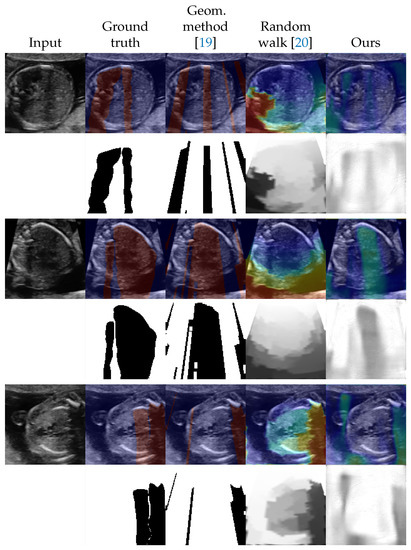

| Method | 0 | 42 (5 Videos) | 90 (10 Videos) | 177 (20 Videos) | 259 (30 Videos) |

| Geometric method [19] | 0.193 (±0.210) | - | - | - | - |

| Random walk [20] | 0.450 (±0.142) | - | - | - | - |

| U-Net [30] | - | 0.610 (±0.184) | 0.655 (±0.170) | 0.681 (±0.136) | 0.698 (±0.137) |

| Ours | 0.578 (±0.164) | 0.666 (±0.142) | 0.686 (±0.148) | 0.707 (±0.113) | 0.720 (±0.151) |